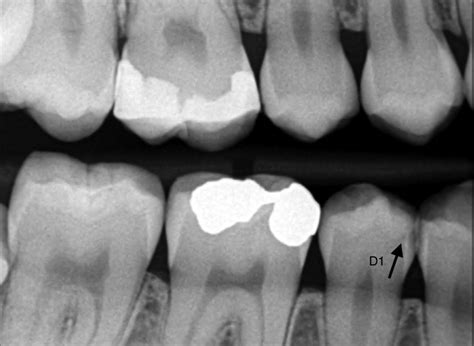

El concepto de muela picada es la forma popular de referirnos a una caries en un molar. Una muela picada, también conocida como caries dental, es una afección muy común que se produce cuando las bacterias presentes en la boca descomponen el esmalte de los dientes, creando pequeñas cavidades o agujeros. Estas cavidades, si no se tratan a tiempo, pueden llegar a afectar la dentina y la pulpa dental, las capas internas del diente.

- Manchas en los dientes: Las caries pueden causar manchas blancas, marrones o negras en la superficie del diente, especialmente en las zonas afectadas. La apariencia de la muela es otro indicativo notable, ya que el sarro suele aparecer antes que la caries, por lo que podrás notar manchas marrones o amarillas en tus dientes.

- Obturación o empaste dental: La obturación o empaste dental es el tratamiento más común y efectivo para curar los dientes picados. Consiste en limpiar toda la caries que afecte al diente y después reconstruir la muela tapando el hueco que ha generado con un material plástico para mantener la cavidad sellada. Es el tratamiento más común y se utiliza cuando la caries es superficial. El dentista elimina la parte afectada del diente y la rellena con un material de relleno, como la resina compuesta, para restaurar la forma y función del diente. Se realiza bajo anestesia local.